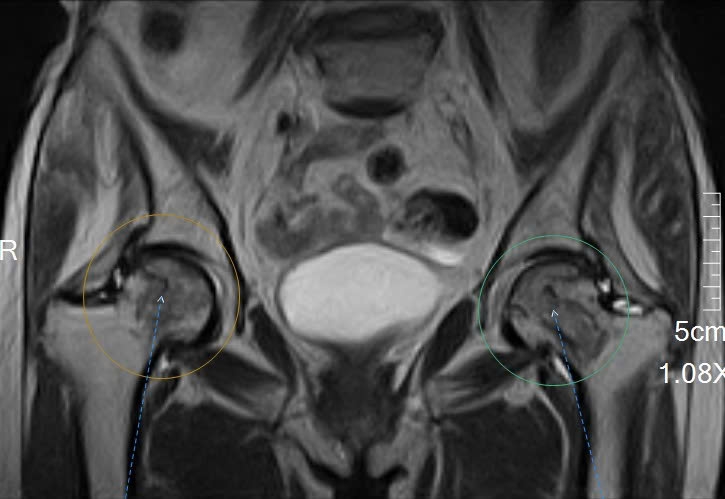

🍎Sau khi thăm khám lâm sàng, bác sĩ chỉ định chụp cộng hưởng từ (MRI) khớp háng để đánh giá chi tiết tình trạng xương và khớp.

Kết quả chụp MRI cho thấy dấu hiệu hoại tử chỏm xương đùi – một tổn thương khó phát hiện nếu chỉ chụp X-quang ở giai đoạn sớm. Nhờ hệ thống máy chụp cộng hưởng từ MRI hiện đại tại Hồng Hoàng, các bác sĩ đã phát hiện bệnh kịp thời, từ đó tư vấn hướng điều trị phù hợp cho bệnh nhân.